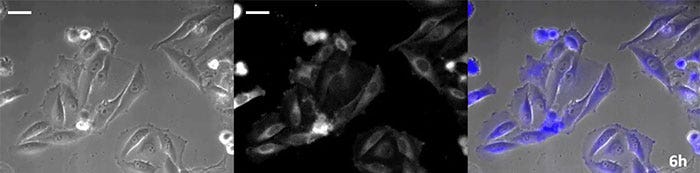

薬効評価を行う上で細胞の経時的な観察は、その影響を詳細に解析するために必要となります。以前より化学発光はルシフェラーゼの成熟時間と半減期が短い特性より、遺伝子発現のレポーターとしてその経時変化を解析することに適すことが知られています。また、蛍光と異なり励起光が不要なため、長時間のイメージングに用いる場合には、細胞に対する光毒性は軽減されます。ただし、化学発光は発光基質 (ルシフェリン) を必要とするため、細胞へのルシフェリンの安定供給が重要です。特に、セレンテラジン (Coelenterazine) 系のルシフェリンは高光度で発光しますが、培地中で短時間に酸化されやすいため、長時間観察を行う場合には適時添加することが必要となります。そこで、高光度化学発光タンパク質を導入した細胞に自動基質添加・培地灌流装置を用いてセレンテラジンを自動添加しながら培地灌流をし、化学発光を経時的に観察した結果、位相差画像と併せて化学発光画像を24時間以上連続して観察することに成功しました(図4)。

0時間後

図4-1 0時間後

6時間後

図4-2 6時間後

12時間後

図4-3 12時間後

18時間後

図4-4 18時間後

24時間後

図4-5 24時間後

図4. 培地の灌流および発光基質の自動添加による長時間観察(スケールバー50µm)